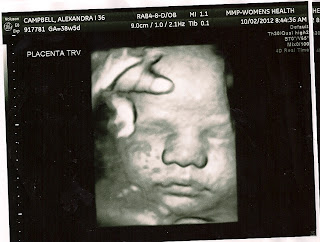

39 week scan!

He really does look a lot like Rafi, in utero, at least.

Rafi's 36 week scan